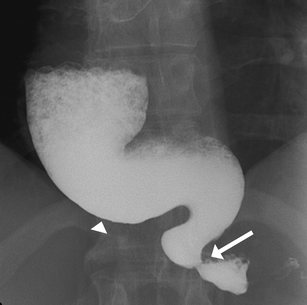

Fig. 2